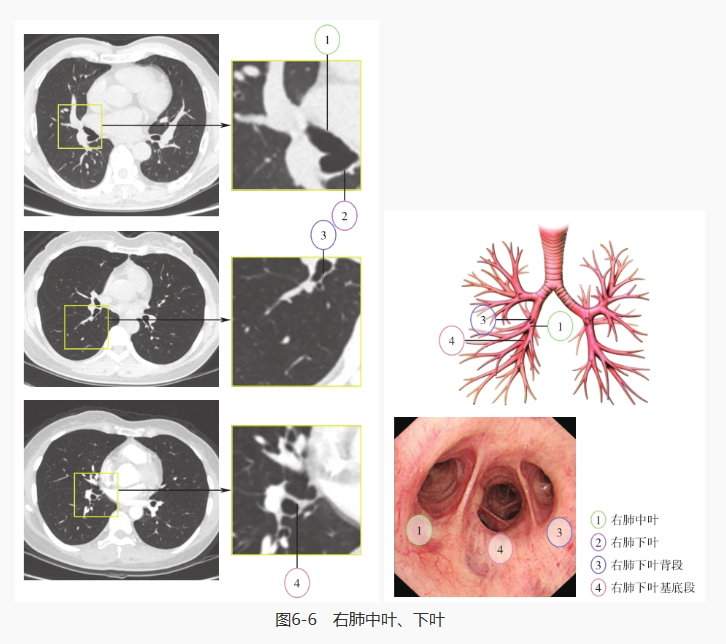

继续探入,先对右肺进行探查,分别是右主支气管、右肺上叶·中间段支气管、右肺上叶、右肺中叶·下叶、右肺中叶、右肺下叶背段和右肺下叶基底段: